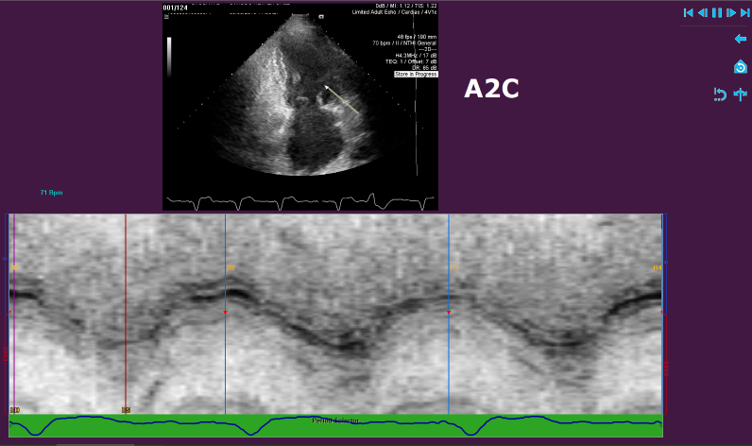

Medis Suite Ultrasound is the latest addition to the Medis Suite portfolio for cardiovascular imaging. Based on 20 years of developments and innovations, we bring you the latest image post-processing tools in advanced cardiac deformation analysis for echo. Medis Suite Cardiac Ultrasound (Echocardiography) is currently available for research use. Medis Suite Ultrasound is a continuation of over 20 years of innovative algorithms and ground-breaking work in Echocardiography software by AMID. AMID was acquired by Medis in 2020.

- Allows the quantitative evaluation of the Left Ventricle, Right Ventricle and the Left Atrium OEM solution. See the applications below for further details